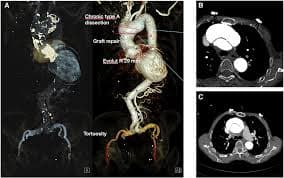

Coronary Angiogram

A CT Coronary Angiogram is a non-invasive imaging test that uses a CT scanner, and contrast dye to create detailed 3D pictures of your heart's arteries, revealing plaque, blockages, or narrowing (stenosis) that can cause heart problems like chest pain.

3D Vessel Analysis

TAVI/TAVR

A TAVI (Transcatheter Aortic Valve Implantation) heart procedure, also known as TAVR, is a minimally invasive way to replace a diseased aortic heart valve using a catheter, avoiding open-heart surgery.

TAVI Procedure

Valve Replacement

Complete Analysis